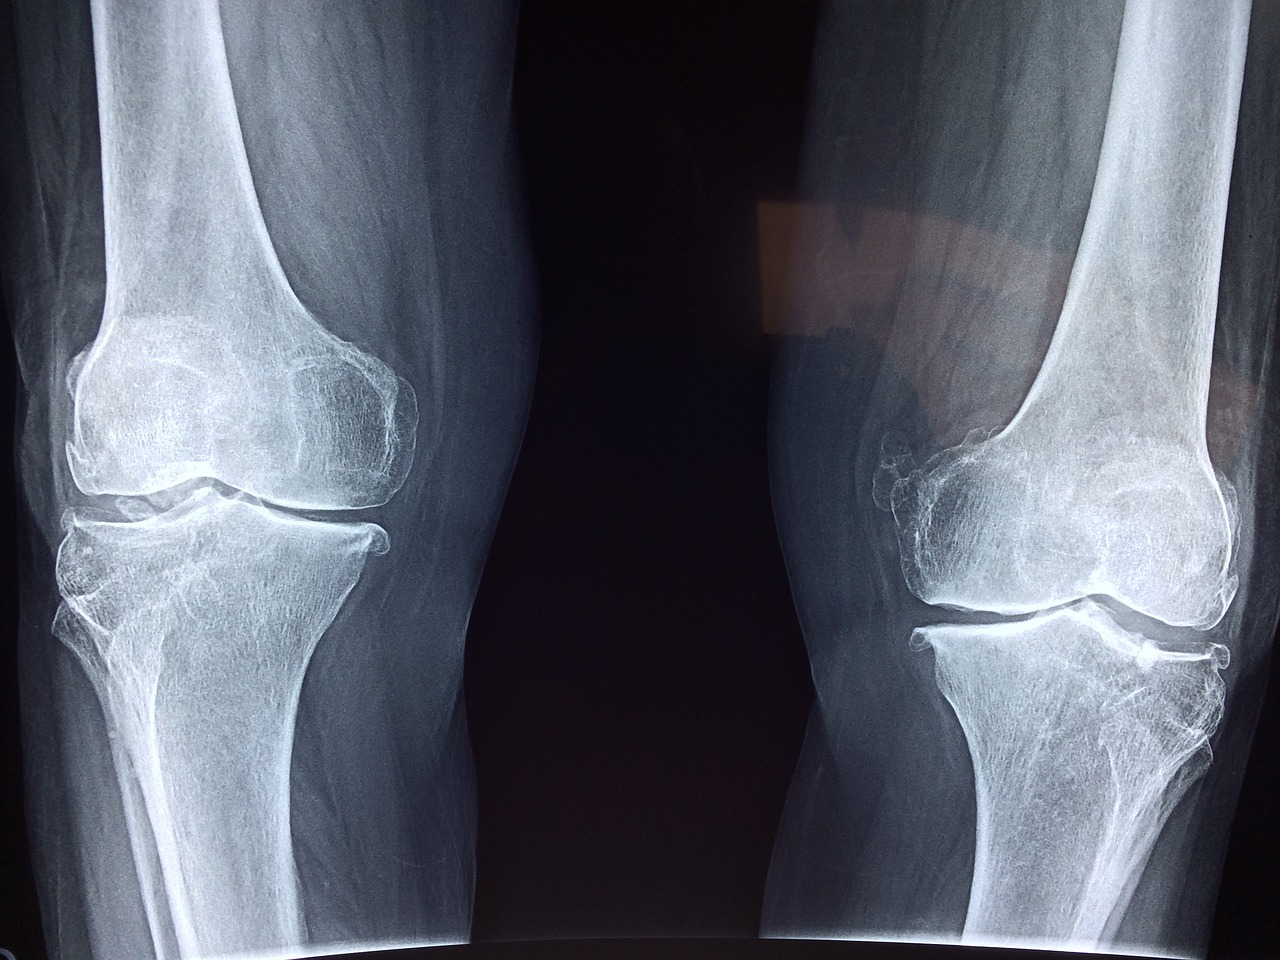

관절염은 다양한 증상을 나타낼 수 있습니다. 흔한 증상으로는 관절 통증과 부종이 있으며, 이로 인해 움직임이 제한될 수 있습니다. 또한 관절이 뭉친 느낌, 아침에 관절 뻐근함, 그리고 관절 주변의 열감 등이 나타날 수 있습니다. 중요한 것은 초기에 증상을 인식하고 조기에 치료를 시작하는 것이 핵심입니다.

관절염의 치료법은 개별적으로 맞춰야 합니다. 약물 치료, 물리치료, 그리고 수술 등 다양한 치료 옵션이 있습니다. 먼저 의사와 상담하여 적절한 치료 계획을 세우는 것이 중요합니다. 일상생활에서는 관절을 피로하게 하지 않도록 주의를 기울이고, 체중을 관리하며 규칙적인 운동을 통해 근력을 강화하는 것도 도움이 될 수 있습니다. 그리고 치료법도 중요하지만